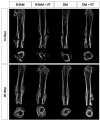

Methods: 148 rats underwent fracture surgery and were assigned to four groups: (1) SHAM: weight-matched non-diabetic rats, (2) SHAM+VT: non-diabetic rats treated with vibration therapy (VT), (3) DM: diabetic rats, and (4) DM+VT: diabetic rats treated with VT. Thirty days after diabetes induction with streptozotocin, animals underwent bone fracture, followed by surgical stabilization. Three days after bone fracture, rats began VT. Bone healing was assessed on days 14 and 28 post-fracture by serum bone marker analysis, and femurs collected for dual-energy X-ray absorptiometry, micro-computed tomography, histology, and gene expression.

Results: Our results are based on 88 animals. Diabetes led to a dramatic impairment of bone healing as demonstrated by a 17% reduction in bone mineral density and decreases in formation-related microstructural parameters compared to non-diabetic control rats (81% reduction in bone callus volume, 69% reduction in woven bone fraction, 39% reduction in trabecular thickness, and 45% in trabecular number). These changes were accompanied by a significant decrease in the expression of osteoblast-related genes (Runx2, Col1a1, Osx), as well as a 92% reduction in serum insulin-like growth factor I (IGF-1) levels. On the other hand, resorption-related parameters were increased in diabetic rats, including a 20% increase in the callus porosity, a 33% increase in trabecular separation, and a 318% increase in serum C terminal telopeptide of type 1 collagen levels. VT augmented osteogenic and chondrogenic cell proliferation at the fracture callus in diabetic rats; increased circulating IGF-1 by 668%, callus volume by 52%, callus bone mineral content by 90%, and callus area by 72%; and was associated with a 19% reduction in circulating receptor activator of nuclear factor kappa beta ligand (RANK-L).

Conclusions: Diabetes had detrimental effects on bone healing. Vibration therapy was effective at counteracting the significant disruption in bone repair induced by diabetes, but did not improve fracture healing in non-diabetic control rats. The mechanical stimulus not only improved bone callus quality and quantity, but also partially restored the serum levels of IGF-1 and RANK-L, inducing bone formation and mineralization, thus creating conditions for adequate fracture repair in diabetic rats.